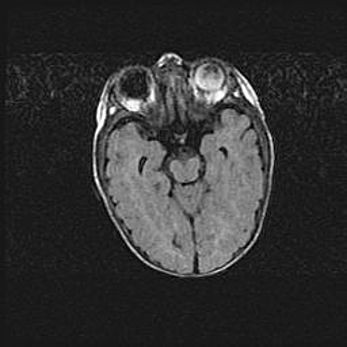

Церебральная ишемия II.

Возраст: 7 дней

Вес: 3350 г

Пол: женский

Окружность головы: 35 см

Срок гестации: 39 недель

Ишемия головного мозга – это состояние, которое развивается в ответ на кислородное голодание вследствие недостаточного мозгового кровообращения. У новорожденных она является следствием дефицита кислорода, что ведет к метаболическим расстройствам различной степени тяжести в тканях головного мозга, в том числе к развитию коагуляционных некрозов и гибели нейронов.